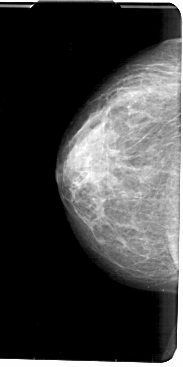

A_1835_1.LEFT_MLO

LEFT_MLO LINES 5491 PIXELS_PER_LINE 2791 BITS_PER_PIXEL 12 RESOLUTION 43.5 NON_OVERLAY